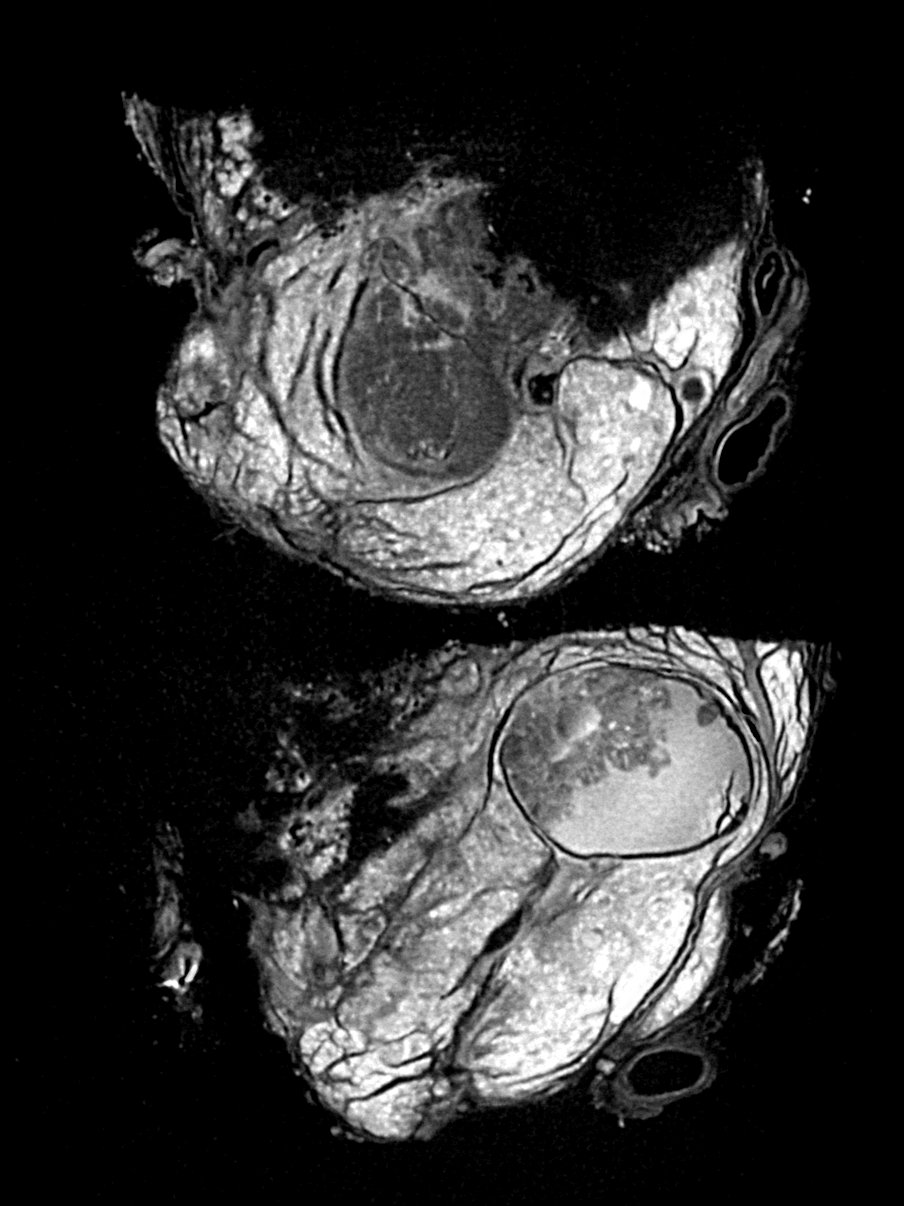

Imaging always involves a trade-off: higher resolution images mean more noise, and longer scans aren’t always practical. DeepDeblur3D is a deep learning model that breaks this trade-off by simultaneously denoising and sharpening 3D micro-CT volumes in a single pass.

The model is a compact 3D U-Net trained on 467 micro-CT volumes covering a wide range of samples, including biological tissue, insects, wood, rocks, and industrial materials, acquired across multiple scanner platforms at Empa. This diversity makes it robust and scanner-agnostic, unlike most existing methods that are tailored to a specific setup.